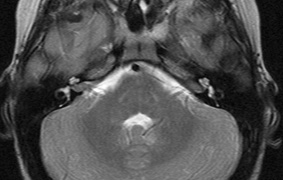

Intracranial leptomeningeal capillary vascular malformation (Figs. 21 and 22) is associated with seizures and contralateral neuromuscular weakness. Central nervous system involvement correlates highly with ipsilateral involvement of the V1 dermatome by a PWS.208,218

Fig. 22. Axial T2-weighted (a) and coronal T1-weighted (b) images of a 16-year-old boy with a port-wine lesion over the right side of his face. The right hemisphere is markedly atrophic and abnormal draining veins are seen within the right lateral ventricle (arrowheads). (c, d) The entire right hemisphere is covered by an enhancing pial angioma and the choroid plexi are enlarged. Enhancing retinal angiomas (arrows), typical of Sturge-Weber syndrome, are seen in (d).